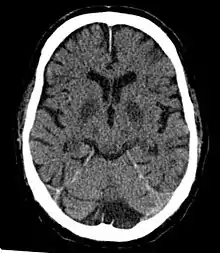

Cerebral hypoxia

Cerebral hypoxia is a form of hypoxia (reduced supply of oxygen), specifically involving the brain; when the brain is completely deprived of oxygen, it is called cerebral anoxia. There are four categories of cerebral hypoxia; they are, in order of increasing severity: diffuse cerebral hypoxia (DCH), focal cerebral ischemia, cerebral infarction, and global cerebral ischemia. Prolonged hypoxia induces neuronal cell death via apoptosis, resulting in a hypoxic brain injury.[1][2]